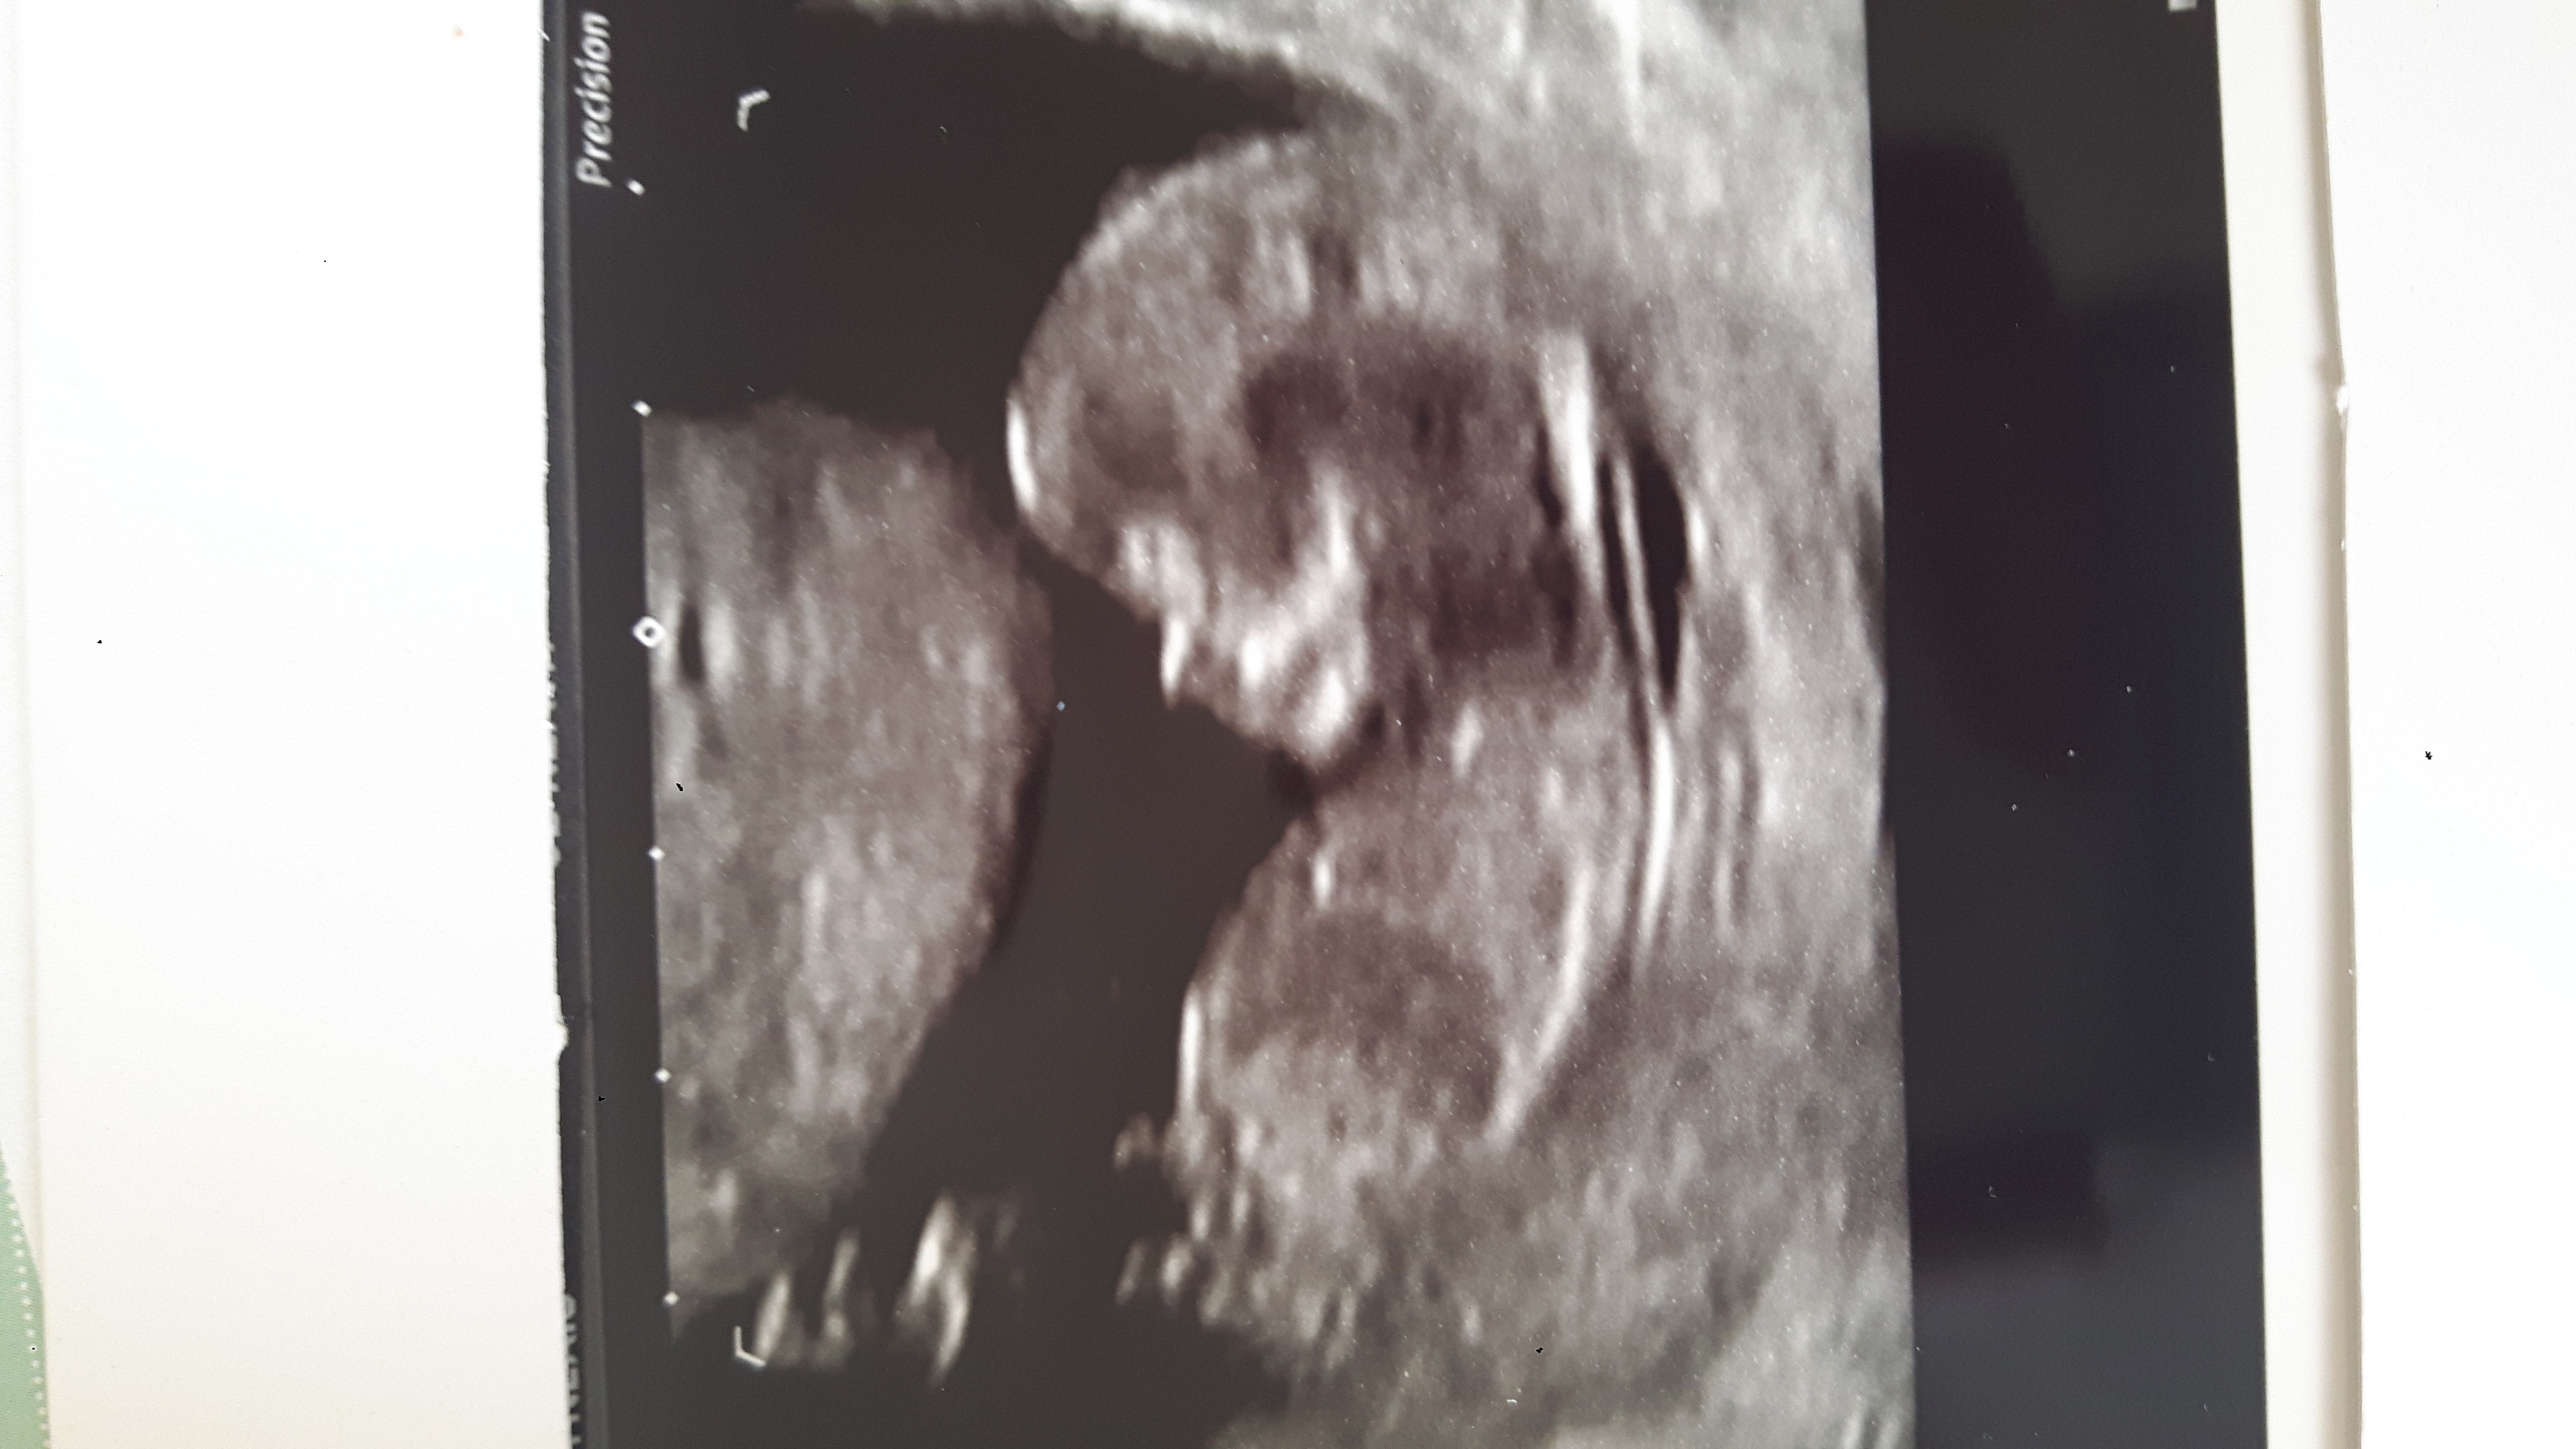

Can you post without your writing? I can't see if the nub is stacked or not.

I see stacking on the nub, so I say boy.

I think boy too, does look a bit stacked.